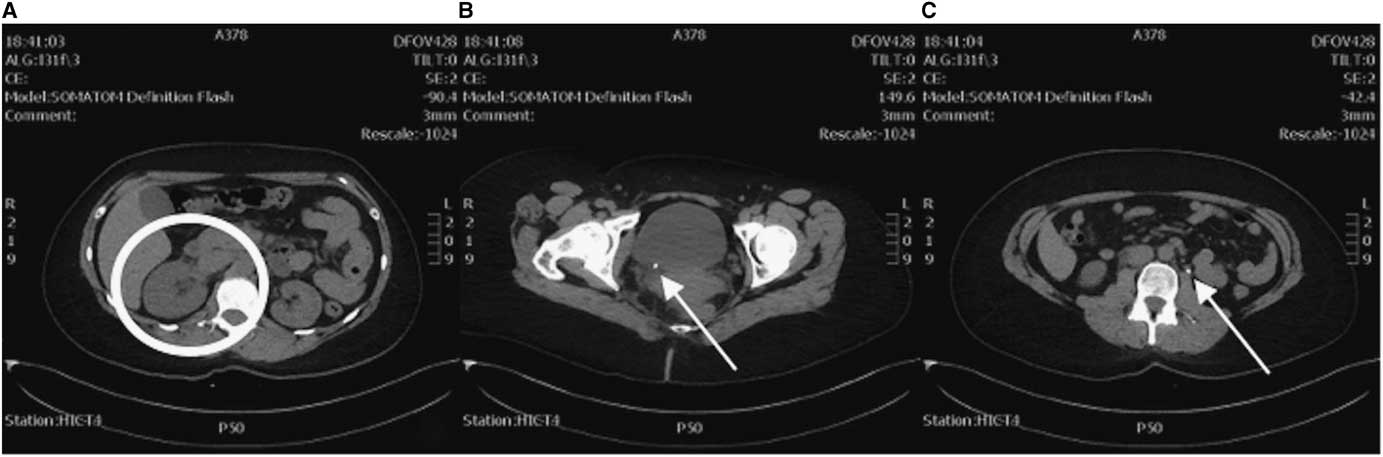

As the clinical course (demonstrated by intractable flank pain) failed to improve over 5 hours with symptomatic therapy and the diagnosis of renal colic yet to be confirmed, an abdominal and pelvic CT was ordered. This study revealed a small 5-mm distal obstructing ureteric calculus at the right vesicoureteric junction causing proximal moderate hydroureteronephrosis (Figure 2). Coincidentally, the CT also revealed another 5-mm left proximal ureteric calculus at approximately the level of the L3 vertebra causing mild ipsilateral proximal hydroureter.

Figure 2 CT axial views. A) Enlarged right kidney indicative of hydronephrosis (circle) compared to the left. B) A 5-mm right distal ureteric calculus at the right vesicoureteric junction (arrow). C) A 5-mm left proximal ureteric calculus (arrow).